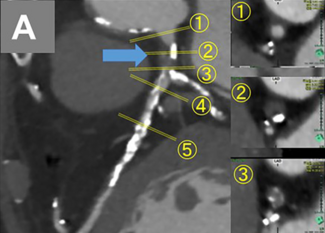

A 55-year-old man presented with medically controlled essential hypertension and a history of abdominal aortic aneurysm stenting 2 years prior who presented with a 3-month history of left lower extremity fatigue on exertion.

05/04/2026

Ping Hu, MD; Xin-yu Wang, MD; Ming Qi, MD; Jie Wang, MD; Xiao-Jing Ma, PhD